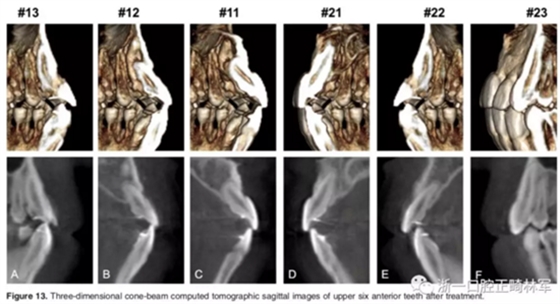

影像學(xué):頭顱側(cè)位片示:矢狀向和垂直向骨骼發(fā)生變化(ANB角,3°;SN-MP,51°);上頜切牙略前傾(U1-SN,106°),與下頜切牙一致(IMPA,75°);病人的面部輪廓得以保持。全景片示:由于牙齒萌出,上前牙區(qū)垂直向牙槽骨水平增加;雖然前牙牙根較彎曲,但其平行度仍可,且無明顯的牙根吸收。CBCT示:前牙唇側(cè)骨質(zhì)連續(xù)性改善,牙根唇側(cè)支持組織變好,牙槽骨高度、厚度均有增加,但轉(zhuǎn)矩的改變一定程度上導(dǎo)致了局部應(yīng)力的增大。